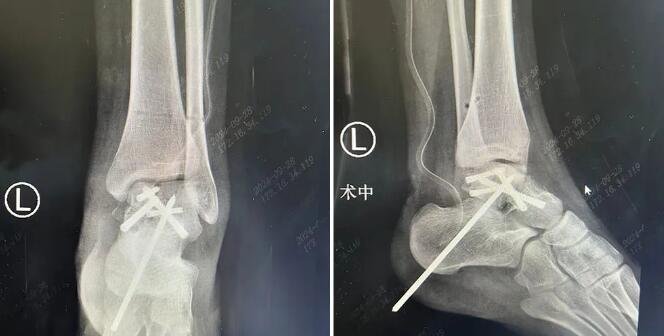

△左踝伤处术后影像

手术过程中,石荣剑、尚军、曹广超等多名sararz骨科专家一齐上阵,针对小蕊各个伤处,分工合作,接力进行。在天玑骨科机器人辅助下,仅打开6处2cm左右的切口,即完成了复杂的脊柱复位和固定操作;通过关节镜下直视复位,每只脚上打开2处1cm左右的切口,将碎成了十余块的骨骼一一复位,并在骨科机器人支持下精准固定。